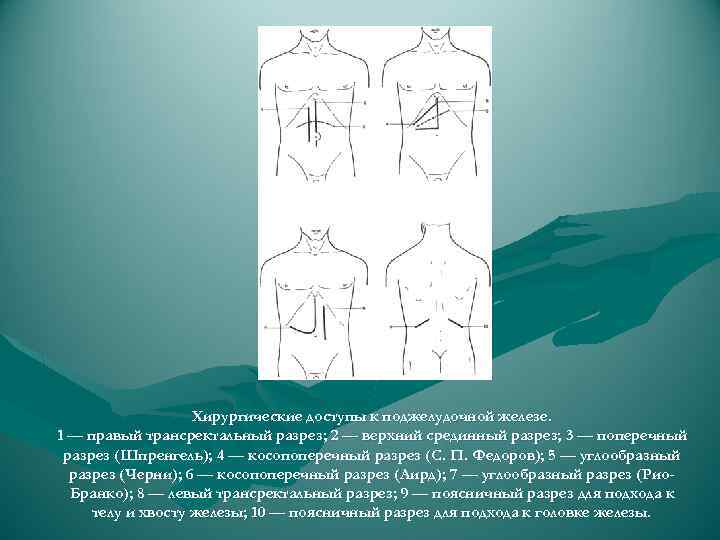

Хирургические доступы к поджелудочной железе. 1 — правый трансректальный разрез; 2 — верхний срединный разрез; 3 — поперечный разрез (Шпренгель); 4 — косопоперечный разрез (С. П. Федоров); 5 — углообразный разрез (Черни); 6 — косопоперечный разрез (Аирд); 7 — углообразный разрез (Рио. Бранко); 8 — левый трансректальный разрез; 9 — поясничный разрез для подхода к телу и хвосту железы; 10 — поясничный разрез для подхода к головке железы.

Хирургические доступы к поджелудочной железе. 1 — правый трансректальный разрез; 2 — верхний срединный разрез; 3 — поперечный разрез (Шпренгель); 4 — косопоперечный разрез (С. П. Федоров); 5 — углообразный разрез (Черни); 6 — косопоперечный разрез (Аирд); 7 — углообразный разрез (Рио. Бранко); 8 — левый трансректальный разрез; 9 — поясничный разрез для подхода к телу и хвосту железы; 10 — поясничный разрез для подхода к головке железы.